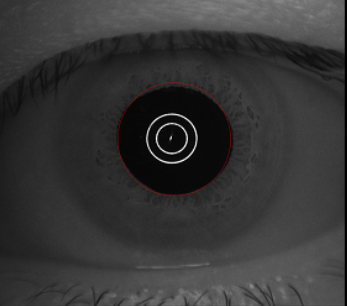

瞳孔直径 PD

参考值:自然光线 2.5-4mm,暗室5-7mm

通过前节影像,可以直观地判断瞳孔是否规则,有无瞳孔缺损、椭圆形瞳孔、虹膜缺失、瞳孔异常等情况。